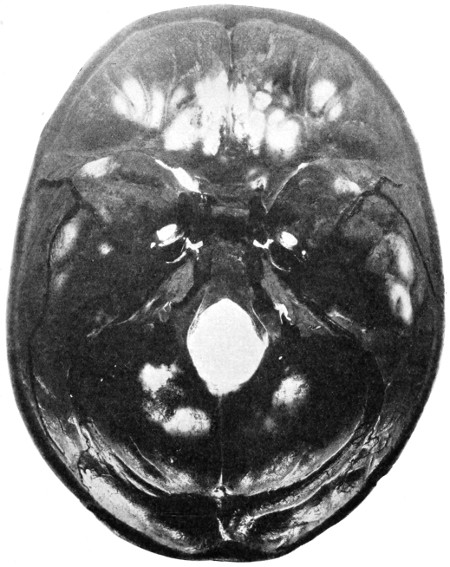

Fig. 1. Cranio-cerebral Topography. 1, The nasion; 2, The inion; 3, The mid-point between nasion and inion; 4, The Rolandic fissure; 5, The superior temporal crest; 6, The inferior temporal crest; 7, The Sylvian point; 8, The anterior horizontal limb of the Sylvian fissure; 9, The vertical limb of the Sylvian fissure; 10, The posterior horizontal limb of the Sylvian fissure; 11, The parietal prominence; 12, The malar tubercle; 13, The lambda; 14, The first temporo-sphenoidal sulcus; 15, The external parieto-occipital sulcus; 16, The lateral sinus; 17, 17, 17, The level of the base of the cerebrum; 18, The external auditory meatus; 19, 19, Reid’s base-line. (Reproduced, by the permission of Mr. H. K. Lewis, from the author’s work on ‘Landmarks and Surface-markings’.)

Fig. 2. Cranio-cerebral Topography. 1, 1, Reid’s base-line; 2, 2, A line parallel to the above at the level of the supra-orbital margin; 3, The middle meningeal artery; 4, The anterior branch; 5, 5, 5, The three sites for trephining; 6, The posterior branch; 7, The site for trephining; 8, The point for trephining to reach the descending horn of the lateral ventricle; 9, The lateral sinus; 10, The inion; 11, The mastoid process; 12, Macewen’s suprameatal triangle; 12a, The mastoid antrum; 12b, The facial nerve; 13, The suprameatal and supramastoid crests; 14, 14, The temporal crest; 15, The temporal fossa; 16, The external angular frontal process; 17, The tendo-oculi attachment; 18, The lachrymal groove. (Reproduced, by the permission of Mr. H. K. Lewis, from the author’s work on ‘Landmarks and Surface-markings’.)